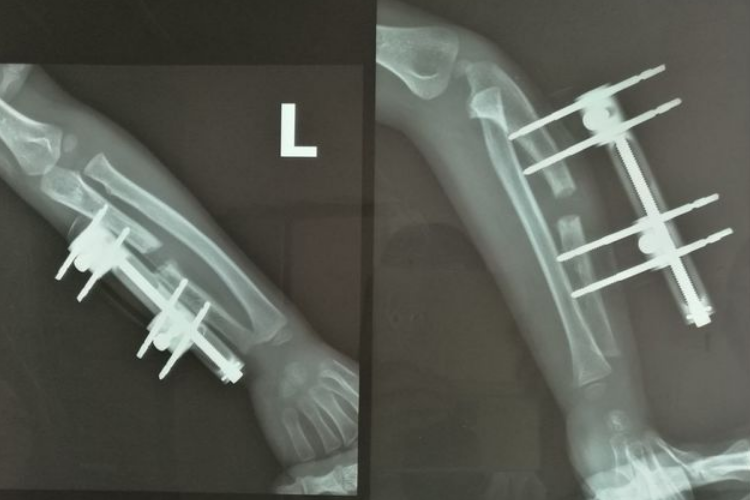

骨痂是骨延长愈合过程中新形成的连接骨折两端的骨组织,骨延长骨痂生长过程中先形成纤维骨痂再形成骨性骨痂。

在骨延长术后两周左右,由于早期大量的纤维细胞、成骨细胞等增殖活动,分泌出大量基质、成纤维细胞和成骨细胞,形成纤维骨痂,可包围并固定骨两端。

纤维骨痂形成后,成骨细胞活跃,分泌出均质透明的类骨基质,继之形成类骨组织,而后钙质在类骨基质间不断沉积形成骨组织,此时骨痂称为骨性骨痂。